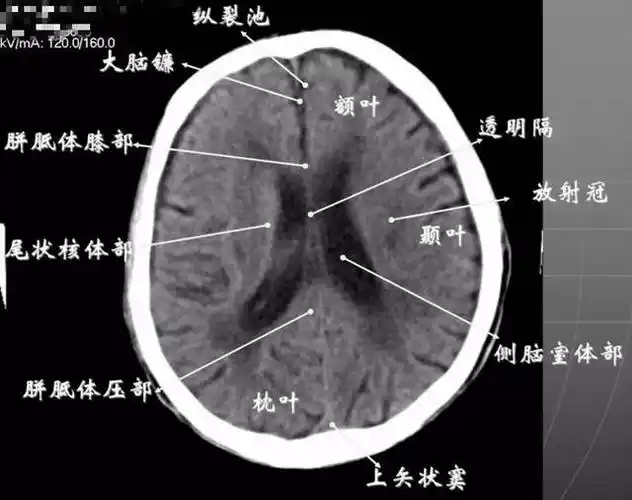

读懂头颅ct并不难,教你成为读片小能手

基底节区层面颅脑ct断层解剖